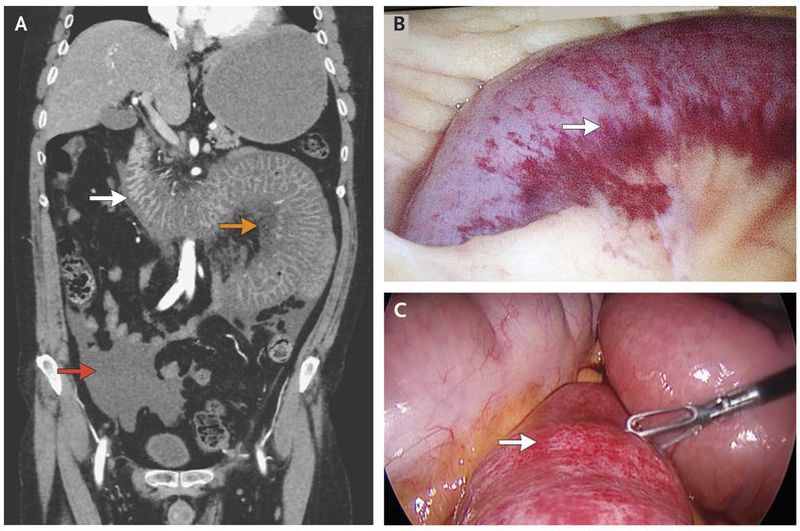

A 48-year-old man who was known to have granulomatosis with polyangiitis was admitted to the hospital for evaluation of an elevated blood creatinine level of 9.5 mg per deciliter (840 μmol per liter; normal range in men, 0.5 to 1.2 mg per deciliter [40 to 110 μmol per liter]). Urinalysis was notable for 2+ protein. The patient, who was positive for antineutrophil cytoplasmic antibody, had been taking azathioprine for 7 years before presentation. Several days after admission, severe abdominal pain developed suddenly, with changes consistent with peritonitis noted on examination. Workup, including computed tomographic angiography, was highly suggestive of bowel ischemia with wall thickening of the distal duodenum and jejunal loops (Panel A, white arrow) with adjacent fat stranding and mesenteric edema (orange arrow) and free fluid in the abdomen and pelvis (red arrow). The patient was taken to the operating room for laparoscopic exploration and was found to have a 40-cm hemorrhagic bowel segment just distal to the ligament of Treitz as well as hemoperitoneum (Panel B shows the involvement of the bowel wall from the mesenteric side and Panel C from the antimesenteric side; the arrow in each panel shows the intraoperative view of hemorrhagic bowel at level of proximal jejunum). The congested hemorrhagic bowel segment was viable, with evidence of active peristalsis, so no bowel resection was performed. This condition was thought to be bowel-wall vasculitis due to granulomatosis with polyangiitis. After surgery, the patient was treated with a heparin drip, and at 48 hours he had minimal abdominal pain. However, he had a persistent elevation of the blood creatinine level. During the same admission, he had rapid progressive worsening of kidney function, and the development of end-stage renal disease necessitated dialysis three times per week. There was no change in his treatment with azathioprine. At a follow-up visit 9 months after presentation, he reported no recurrent abdominal pain, there were no new manifestations of granulomatosis with polyangiitis, and he was receiving permanent renal-replacement therapy.